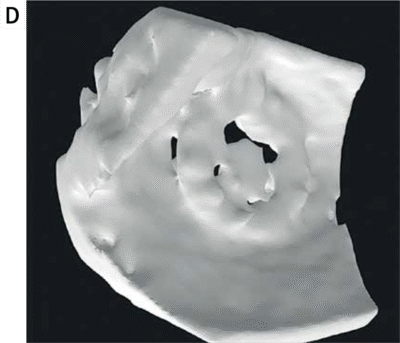

Zespół z GCM i ŚUM wykorzystał dane z echokardiografii 3D-TEE, które po konwersji do plików 3D, dzięki segmentacji w oprogramowaniu powiązanym z drukarką 3D (slicer), zostały wydrukowane w rzeczywistej skali na drukarce Stratasys Objet 30 (v.3) w technologii PolyJet.

Do druku modeli użyto materiałów sztywnych (IORA Model i IORA Support dla koniecznych w pracy drukarki podpór, oba firmy Isquared). Na drukarce Objet 30 uzyskać można wysoką dokładność odwzorowania struktur anatomicznych z odchyleniem nieprzekraczającym ±100 μm przy modelach poniżej 100 mm długości.

W projekcie przeanalizowano 8 przypadków pacjentów z PVL w mitralnych zastawkach mechanicznych lub biologicznych. W testach symulacyjnych przeprowadzonych na wydrukowanych modelach, dobrano optymalne rozmiary okluderów, co później porównano z rzeczywistym postępowaniem klinicznym.

- Modele drukowano w skali 1:1

- Wydrukowano z materiału sztywnego, przezroczystego

Modele drukowane w technologii 3D na podstawie danych z TEE umożliwiają dokładne odwzorowanie przecieku i symulację interakcji okludera z tkankami oraz zastawką. Zdecydowanie wpływa to na skuteczność i bezpieczeństwo zabiegów.

Modele wydrukowane na drukarce Objet 30 odwzorowały strukturę przecieków z wystarczającą precyzją – dzięki temu zespół medyczny mógł realistycznie przetestować różne konfiguracje okluderów jeszcze przed zabiegiem. To znacząco wpłynęło na trafność doboru strategii leczenia.

Górnośląskie Centrum Medyczne i Śląski Uniwersytet Medyczny wdrożyły druk 3D PolyJet od Stratasys do planowania zabiegów zamknięcia przecieków okołozastawkowych. Technologia pozwoliła na stworzenie anatomicznie wiernych modeli serca na podstawie danych z echokardiografii 3D-TEE.

Modele drukowane w skali 1:1 umożliwiły symulację zabiegów, testowanie różnych typów i rozmiarów okluderów oraz ocenę ich interakcji z zastawką i tkankami. W 7 z 8 przypadków dobór okludera na modelu pokrywał się z decyzją kliniczną, co przełożyło się na większe bezpieczeństwo i skuteczność procedur.